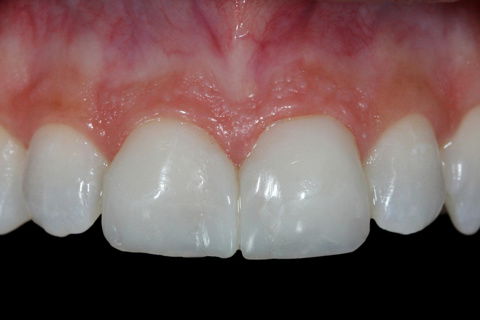

Paciente do sexo feminino, compareceu ao consultório queixando-se das restaurções tipo Classe IV dos elementos 11 e 21. A mesma relatou que havia sofrido uma queda da bicicleta há dois meses, o que havia causado as fraturas extensas dos dentes. No exame radiográfico e clínico nenhum comprometimento endodôntico. Foi proposto clareamento conjugado e duas facetas em resina direta nos elementos envolvidos.

Fotos do caso